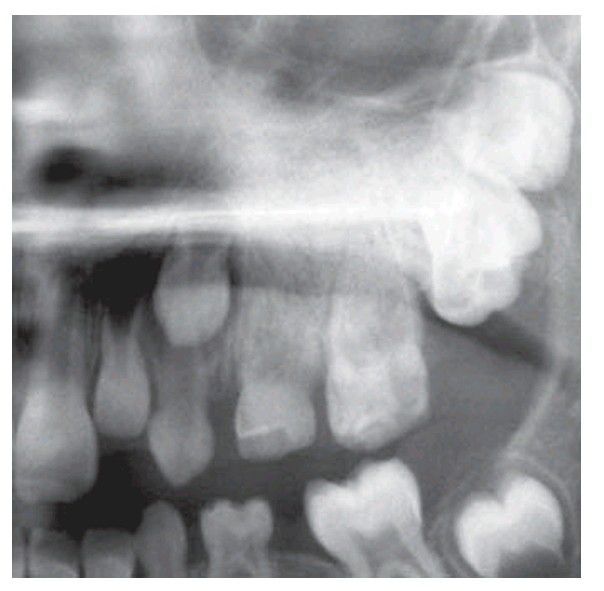

Segmental odontomaxillary dysplasia

Segmental odontomaxillary dysplasia showing abnormal upper primary molars that are indistinct against a background of even, coarsely trabecular bone. Permanent successors are absent.